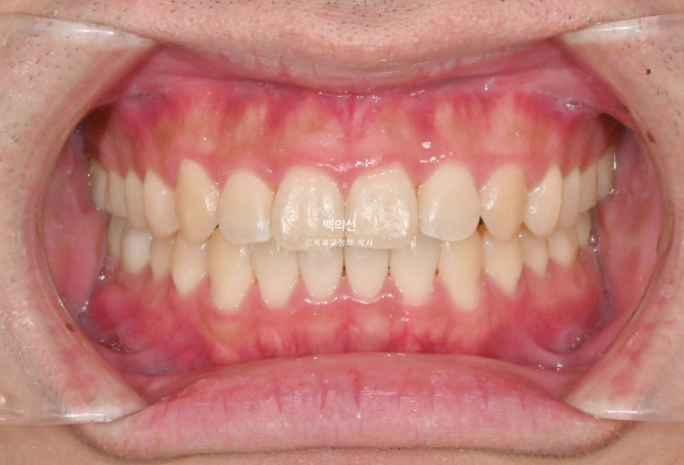

25.05

중심선은 잘 맞고

교합은 좋습니다.

치료 전 후 비교해보겠습니다.

좌 치료 전 / 우 치료 후

24.01~25.05

총 치료기간은 1년 4개월이며 인비절라인으로 치료한 기간은 9개월 입니다.